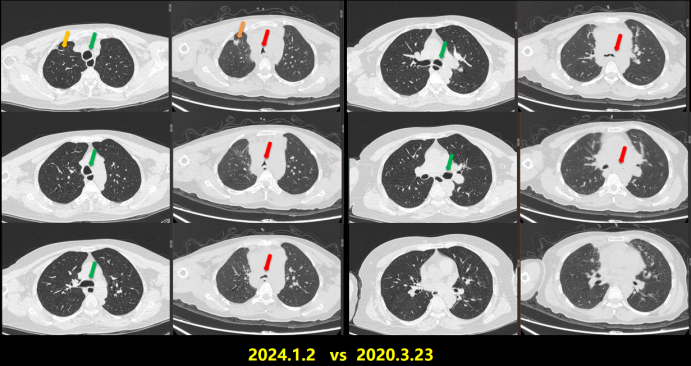

病例5:63岁女性患者,因呼吸困难20天、加重1天入院患者20天前无明显诱因出现活动性气促,伴心悸、咳嗽、咳白痰;1天前患者呼吸困难症状加重,稍行走5米后即气促严重;指脉氧饱和度72%,氧合指数64.2 mmHg(HFNC:流量55 L/min,吸氧浓度95%),查肿瘤指标CEA>1000 ng/ml予气管插管机械通气。床旁纤支镜可见气管膜稍充血,未见明确新生物,分泌物少病理提示红细胞背景中见大量腺癌细胞,免疫组化符合肺腺癌。患者诊断为肺腺癌伴纵隔淋巴结、双肺内及胸腰椎多发转移。基因检测结果提示存在EGFR经典突变(19外显子缺失)。给予靶向治疗联合抗感染、营养支持及免疫调节等治疗,患者气促明显改善,胸部CT示双肺多发病灶显著吸收(图8)1周后拔管脱机,2周后出院,逐步恢复居家生活,目前仍在长期门诊随访

图片

8  患者治疗前后胸部CT对比